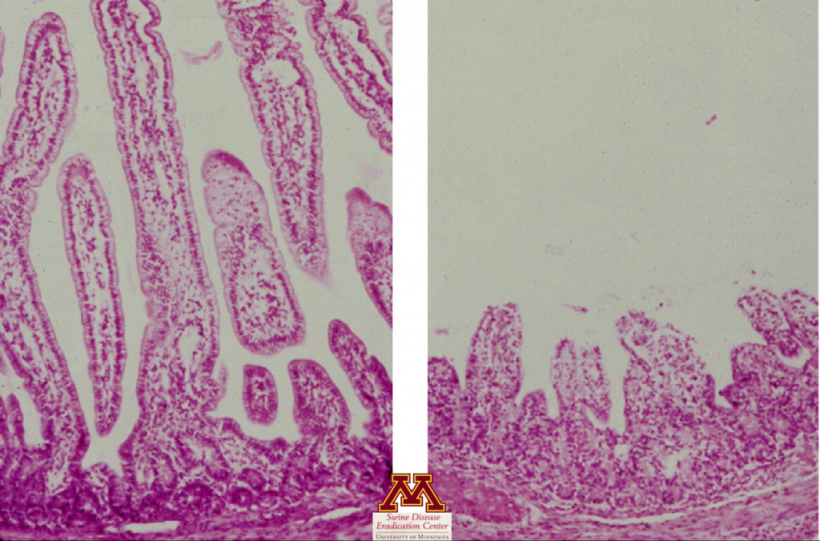

- Avalia a presença de lesões teciduais (atrofia das vilosidades do intestino delgado) que podem sugerir fortemente a presença de doença.

- Confirma atrofia das vilosidades sugerindo enterite viral

- Positivo: Confirmação da doença, mas não da causa da doença.